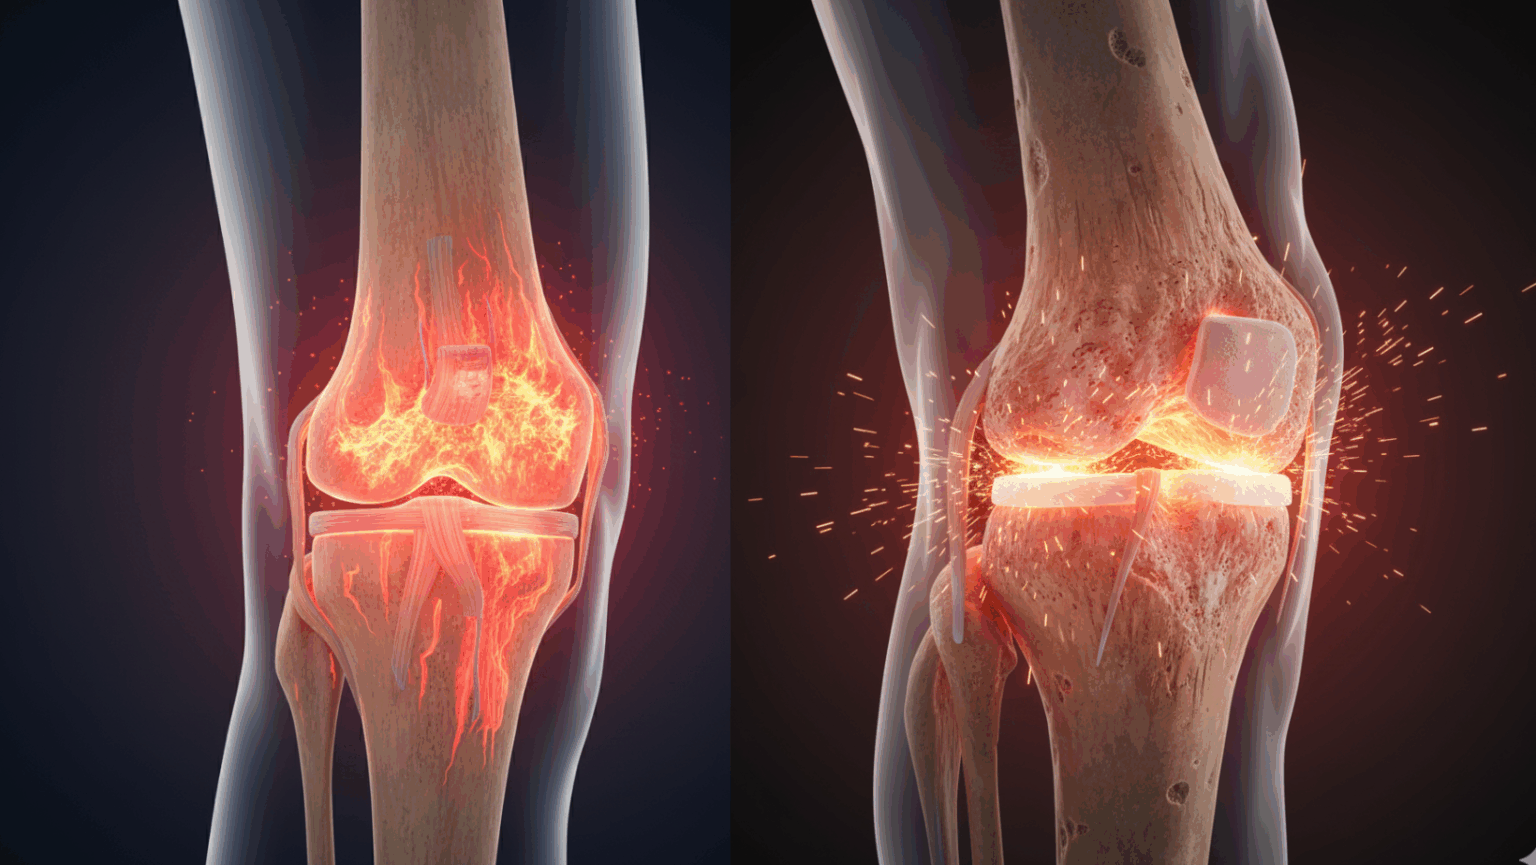

Take a look at the results of the VEGAN-D Effect On your Joints

So How Does Vegan-D Work?

See Step By Step How Vegan-D Fixes Your PAIN Forever

STEP 2 – Plant-Based Vitamin D Floods Your System

Within hours, your body absorbs the dual-source D3 + D2 formula. Your cells immediately start producing the healing compounds your joints have been starving for.

STEP 3 – Watch Your Body Heal Itself Naturally

Day by day, inflammation reduces. Joint lubrication returns. Pain fades. You sleep peacefully. You move freely again.